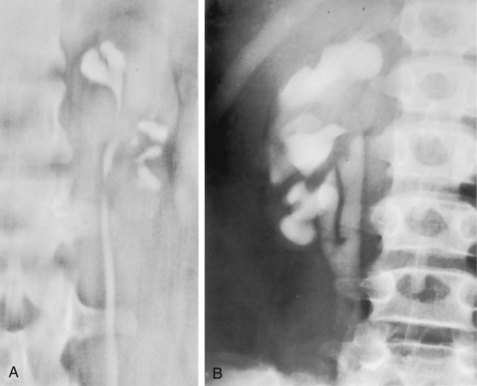

Chronic pyelonephritis describes a shrunken, scarred kidney, diagnosed by morphologic, radiologic, or functional evidence of renal disease that may be postinfectious but is frequently not associated with UTI. Bacterial infection of the kidney may cause a focal, coarse scar in the renal cortex overlying a calyx, almost always accompanied by some calyceal distortion (Fig. 10–1), which can be detected radiographically or by gross examination of the kidney. Less commonly, renal scarring from infection can result in atrophic pyelonephritis or generalized thinning of the renal cortex, with a small kidney appearing radiographically similar to one with postobstructive atrophy (Fig. 10–2).

Figure 10–2 A, Excretory urogram of the contralateral left kidney from the same patient as in Figure 10–1. The severe pyelonephritic atrophy, undoubtedly caused by febrile urinary infections during early infancy with reflux into different segments of the kidney, produced irregular cortical scarring. Note how all the calyces extend to the capsule with irregular, intervening areas of cortex. B, Pyelonephritic atrophy, suggestive of postobstructive atrophy, in a 20-year-old woman with spina bifida, neurogenic bladder, and many episodes of fever and bacteriuria in early childhood. Observe the uniform, regular atrophy of the renal cortex that suggests reflux of bacteria simultaneously into virtually all nephrons. This type of pyelonephritic atrophy is uncommon compared with that shown in A and is characteristic of obstruction with superimposed infection.